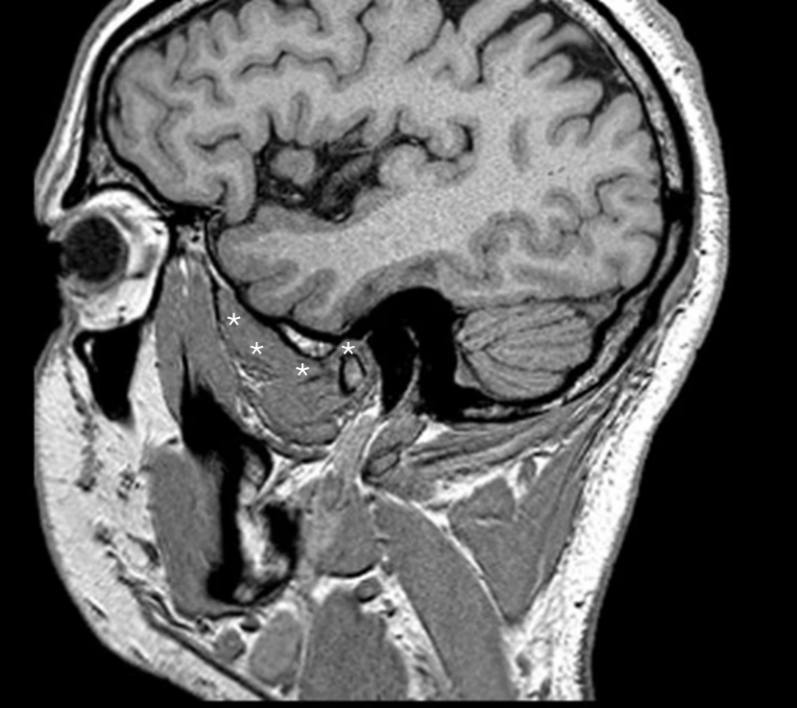

2.104 In der Abbildung zeigt sich ein MRT-Schädel in Sagittaler Rekonstruktion. Mit Sternen markiert ist ein Muskel. Um welchen Muskel handelt es sich?

- (A) M. masseter

- (B) M. temporalis

- (C) M. pterygoideus medialis

- (D) M. pterygoideus lateralis

- (E) M. buccalis